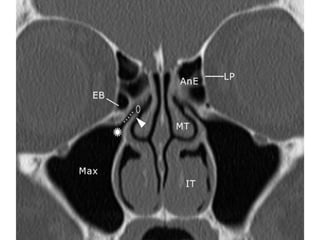

Ethmoids-ant and post

vertical attachment of basal

lamellae to anterior skull base

Ethmoidal sinus

• basal lamellae of the middle turbinate

separates the ethmoid into anterior and

posterior groups with different drainage

patterns

• Ant cells form 1st followed by the posterior

cells.They are not seen on radiographs

until age one

• Lateral wall-Formed by the orbital plate of

the ethmoid,known as the lamina

papyracea.this wall could be dehiscent-

route of spread of infection

. The transition of thick fovea to the thin

portion of roof of ethmoid medially is very

weak-injuries during surgery leading on to

CSF leak.